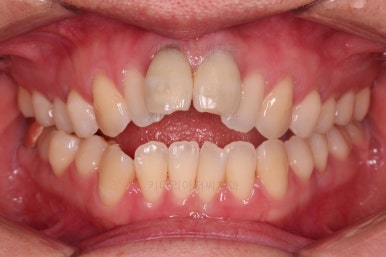

1. 초진

부산개방교합 키다리아저씨치과에 처음 내원 시 입안의 모습입니다.

전반적으로 치열이 삐뚤고요.

앞니쪽이 다물어지지 않는 개방교합(오픈바이트, open bite) 을 보였습니다.

어금니 맞물림을 보면 앵글씨 2급 부정교합 양상이어서 위아랫니가 모두 1대1로 부딪히고 있는 상태였습니다.

2급 부정교합인 분들의 특징이 앞니가 튀어 나와 있어서 돌출입 양상을 보이는 경우가 많습니다.

개방교합이어서 윗니 앞니가 들려 올라가서 심미적으로 좋지 못한 상황이었고요.